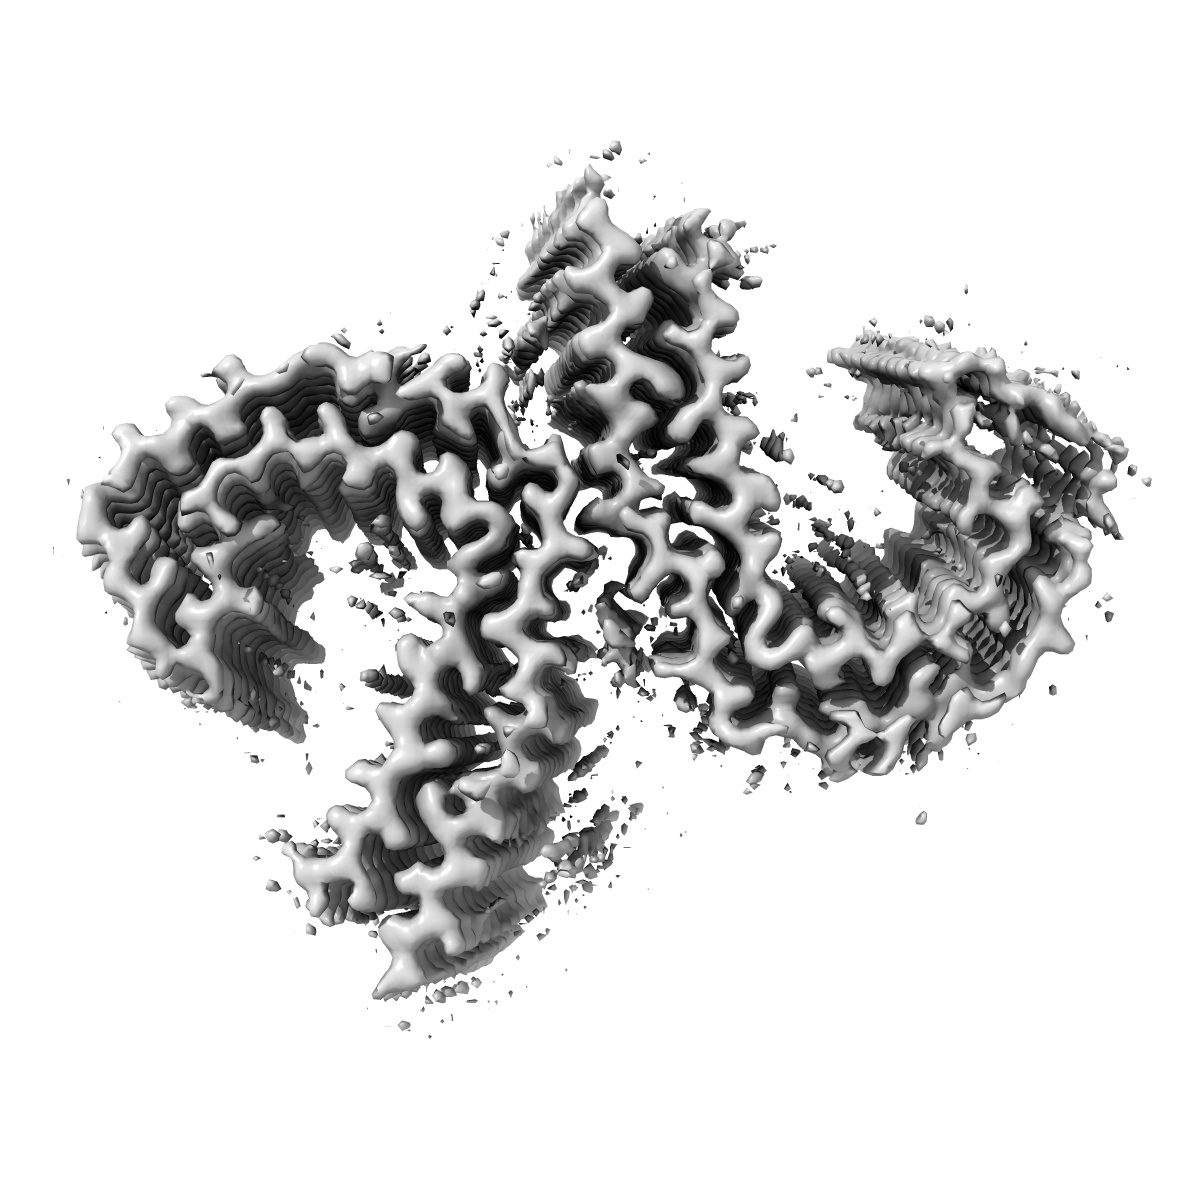

Straight Filament of tau amyloids found in Down Syndrome individuals

EMD-45007

Helical reconstruction

3.0 Å

Sample Organism: Homo sapiens

Sample: Straight Filaments purified from Down Syndrome individual brain tissue

Fitted models: 9bxo

Deposition Authors: Tse E, Ghosh U, Condello C , Southworth D

Cryo-EM structures reveal tau filaments from Down syndrome adopt Alzheimer's disease fold.

Ghosh U, Tse E, Yang H , Shi M, Caro CD, Wang F, Merz GE, Prusiner SB, Southworth DR, Condello C

(2024) Acta Neuropathol , 12 , 94 - 94